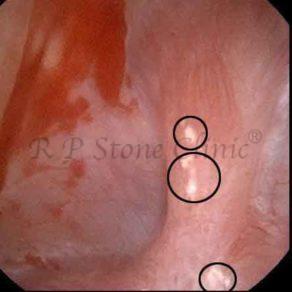

These images are taken as snap shots from the video recording of RIRS Surgery done at our hospital. These are Randall’s Plaques seen with Digital FLEX XC & Digital FLEX XC S. The cream or whitish patches are seen on the tips of RENAL PAPILLAE as seen in images below.

The Below Images Show Small Stones attached to the Renal Papillae.